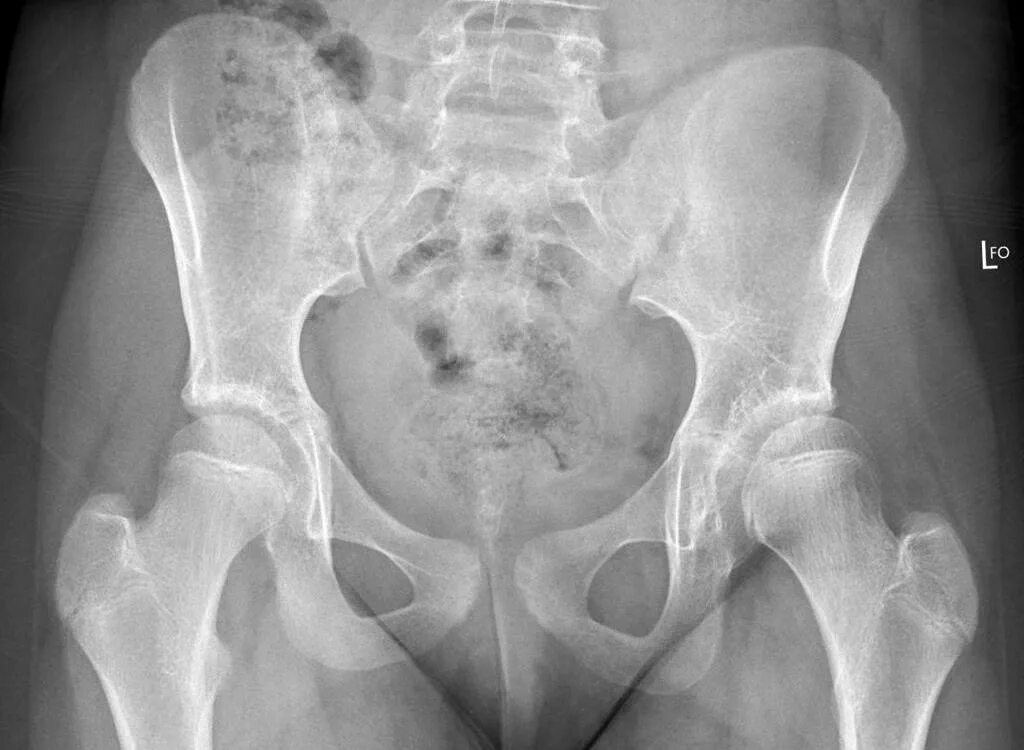

Дисплазия тазобедренного сустава мкб 10